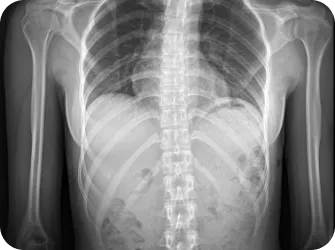

척추 엑스레이 검사

목 커브와 휘어짐 측정

좌우 어깨 높이와 틀어짐 측정

좌우 골반 수평 및 비틀림 측정

흉추,요추 만곡/ 척추 휘어짐 측정